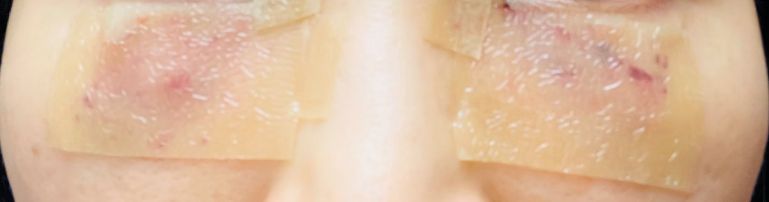

한관종 치료를 받은 다음날 모습입니다.

한관종 치료를 받고 적어도 화장을 했을 때 흉터가 가려지려면 2주는 지나야 합니다. 그러나 저는 치료 부위의 면적이 넓기 때문에 그런 것이고 저보다 가벼운 수준이라면 2주가 걸리지 않을 수도 있습니다.